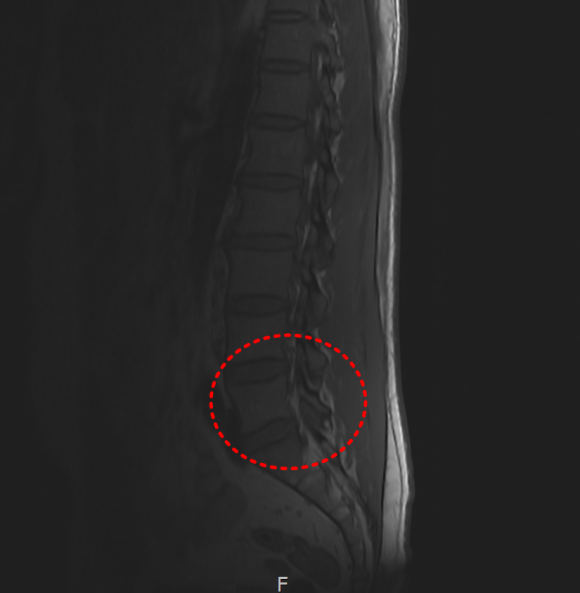

어깨 충돌증후군 & 회전근개파열양쪽 발목 골절 & 인대 완전파열SLAP 파열 & 일자허리일자목 & 디스크 팽륜햄스트링 파열대퇴사두근 파열

일자목 & 디스크 팽륜